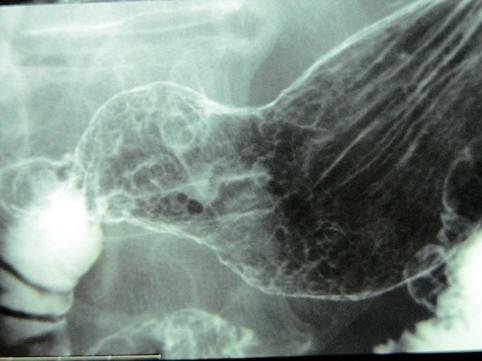

症例提示(所在地,施設名等): 東京都・ 国立がんセンター中央病院

疾患(病理主体)の分類悪性リンパ系腫瘍/悪性リンパ腫

部位(臓器別)胃(部位)/前庭

検査方法X-P

腫瘍の肉眼分類0型(表在型)/IIc型(IIc)

病変の最大径(ミリ)40以上

腫瘍の深達度sm